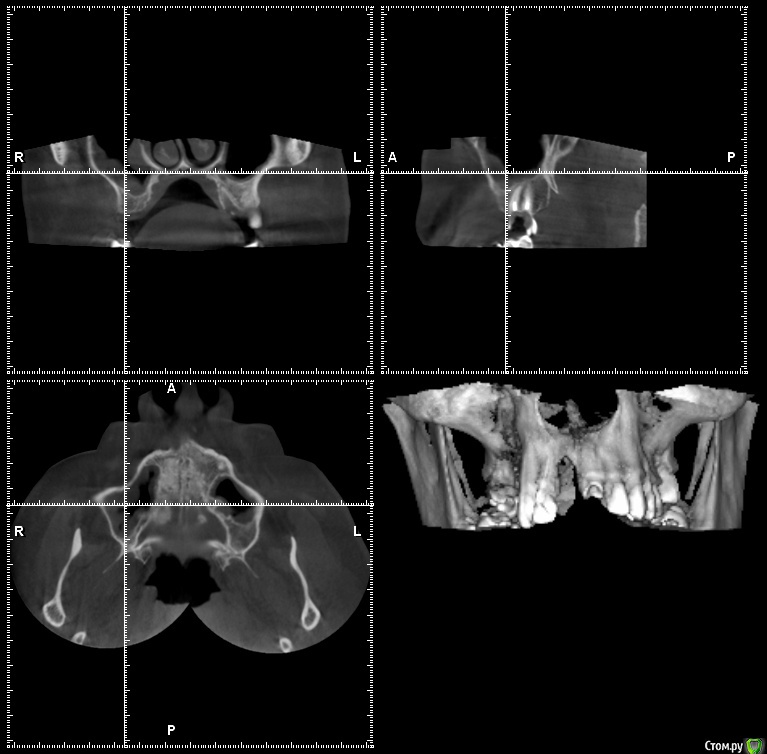

gum Опубликовано 30 июня, 2015 Поделиться Опубликовано 30 июня, 2015 Коллеги подскажите. Лор потом синуслифт или возможен сразу синуслифт Ссылка на комментарий

Alejandro Опубликовано 30 июня, 2015 Поделиться Опубликовано 30 июня, 2015 + 1 за ЛОРа, но только такого, который не скажет - "никаких имплантов, они выпадают" Полностью согласен! Соустье есть на КТ? Ссылка на комментарий

gum Опубликовано 30 июня, 2015 Автор Поделиться Опубликовано 30 июня, 2015 Соустья нет. Направил пациента к ЛОРу. К концу недели узнаю результат Ссылка на комментарий